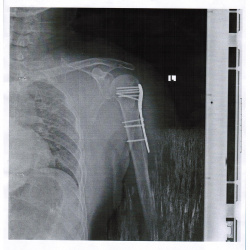

На данном сайте и не только, часто спрашивают - есть ли вывих плеча? Часто при травмах, переломах верхнего конца плечевой кости, при стандартных снимках, бросается в глаза низкое...

Перелом и подвыв головки плечевой кости? М 55 лет. Упало 3 дня назад подозрение на перелом головки плечевой кости. Головка поднята доверху, есть ли подвивы или перелом?